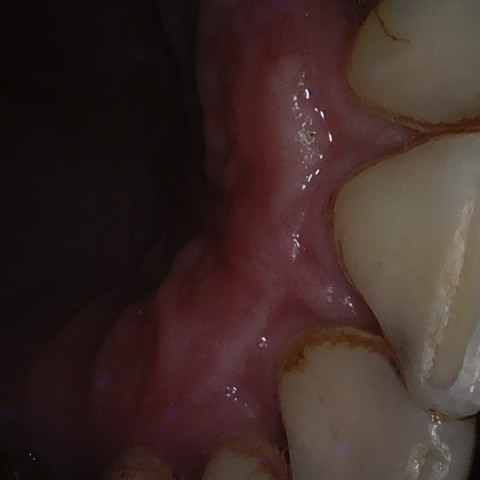

Image 362 / 1743

NHD36692

Annotated as "Good"

Original Image Rendering Image